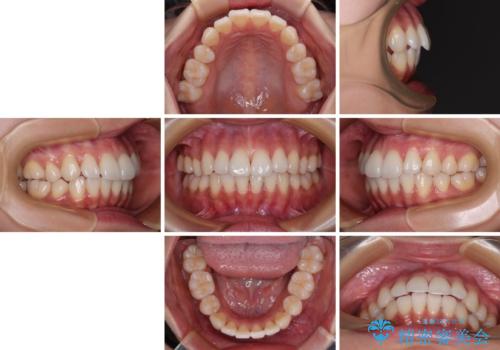

1. 開始前

2. 治療途中

3. 終了時

1. 抜歯矯正の軽度後戻りを解消 インビザライン矯正の治療前

2. 抜歯矯正の軽度後戻りを解消 インビザライン矯正の治療中

3. 抜歯矯正の軽度後戻りを解消 インビザライン矯正の治療後